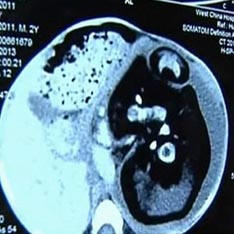

Hirurzi su njegovo nerođeno pronašli u stomaku dvogodišnjeg djeteta Sijamski blizanci. S neobičnim slučajem u svojoj praksi suočili sa ljekarima iz Kine. Nakon pregleda ljekara dvogodišnji dečak ogromnog trbuha iz sela Huashi, ispostavilo se da je u njemu njegov nerođeni brat blizanac. Odlučeno je da se izvrši hitna operacija, jer mu je želudac natečen nevjerovatne veličine, unutrašnji organi su se počeli stisnuti, i bebi je postalo teško disati, piše Daily Mail. Ispostavilo se da je brat, koje je sve vrijeme bilo u njemu, nije bilo mnogo manji od samog dječaka. Tijelo mu je bilo nerazvijeno, ali kičma, udovi i prsti na rukama i nogama su u potpunosti oblikovani. Ovaj slučaj, objasnili su ljekari, jedna je od sorti sijamke blizanci. Nastaju kada je oplođeno jaje nije u potpunosti deljeno. Ali, kao što je napomenuo neonatolog iz rasadnika Jonathan Fanarof iz bolnice u Clevelandu, u slučaju “trudna” beba, jaje se nije delilo.

U čitavoj istoriji medicine postoje stotine slučajeva kada je jedan blizanačkih embriona “apsorbira” njegov brat i nastavlja razvoj unutar nje. Ova pojava se uvek pojavljuje rano. stadija trudnoće, a obično oba ploda umiru u maternici majke. Dešava se, međutim, da je porođaj uspješan i uhvaćen zametak zamke i dalje živi kao parazit spojen na njega stariji brat neka vrsta pupčane vrpce. Na kraju on postaje toliko velik da počinje samo da šteti vlasniku. U medicini se ta anomalija naziva fetus in fetu (embrion u embrionu). Usput, zabilježen je isti slučaj pre nekoliko godina u Indiji. Trbuh 36-godišnje Sanju Bhagat bio je toliko nabrekao da je izgledao kao žena koja se spremala rodiće. Hirurzi su bili sigurni da je imao ogroman tumor, koji pritišće na dijafragmu. Ali kakvo je bilo njihovo iznenađenje kad su ostali van njega izveli su iz maternice mutirano tijelo njegovog brata blizanca.